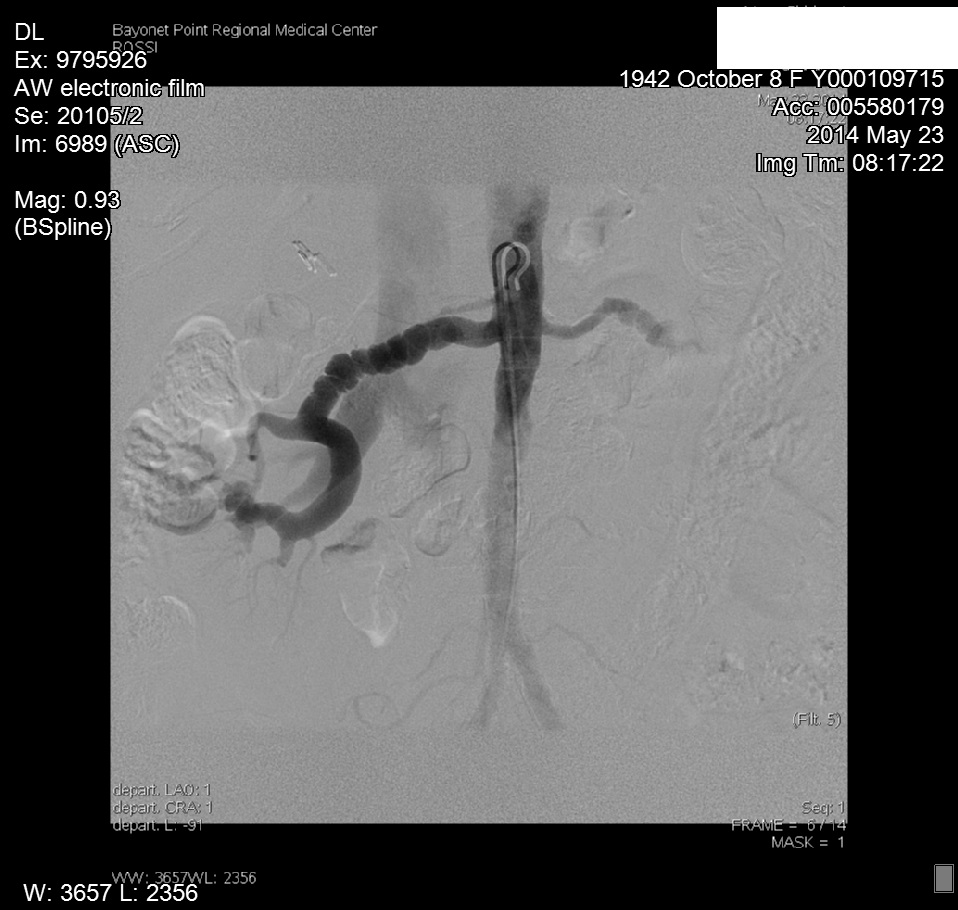

Upon obtaining the abnormal doppler findings, our interventional cardiologist performed an abdominal angiogram with selective bilateral renal arteriography. The angiogram demonstrated diffuse right renal artery haustra consistent with FMH. As well, abnormal retograde filling of the right renal vein and IVC was noted, and consistent with an AV fistula within the right renal artery helium (Figure 4). The left renal artery was normal on preliminary imaging, but remained suspect. Upon IVUS (Intra Vascular Ultra Sound) imaging, a significant (20mm) gradient was noted within the left distal renal artery.3 Bilateral cutting balloon angioplasties were performed and the patient was then sent to CPRU for recovery (Figure 5 & 6).

Figure 5 Angiogram images of RRA FMD.

Figure 6 Angiogram images of RRA FMD.